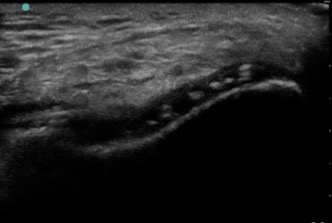

Knee Anterior Trochlear Cartilage Calcium Pyrophosphate Crystal Deposition Image